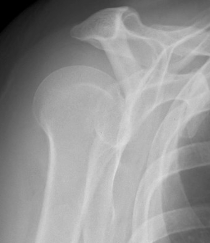

Normal scapular lateral

Posterior shoulder dislocation